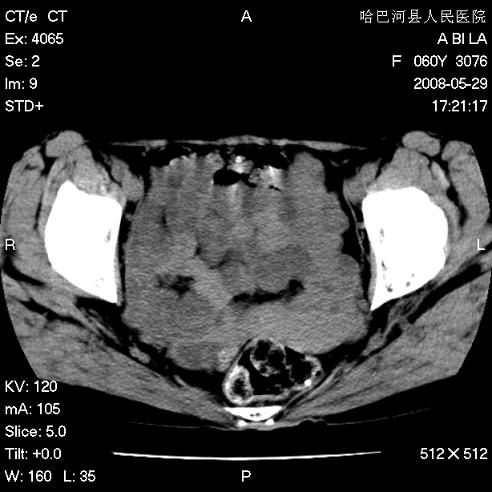

标题: CT13730:排尿不畅4天,抗炎治疗无效,现尿中可见血块 [打印本页]

标题: CT13730:排尿不畅4天,抗炎治疗无效,现尿中可见血块

膀胱内多发恶性占位,癌可能性大

手术结果及病理:膀胱癌并膀胱壁转移,膀胱内血块